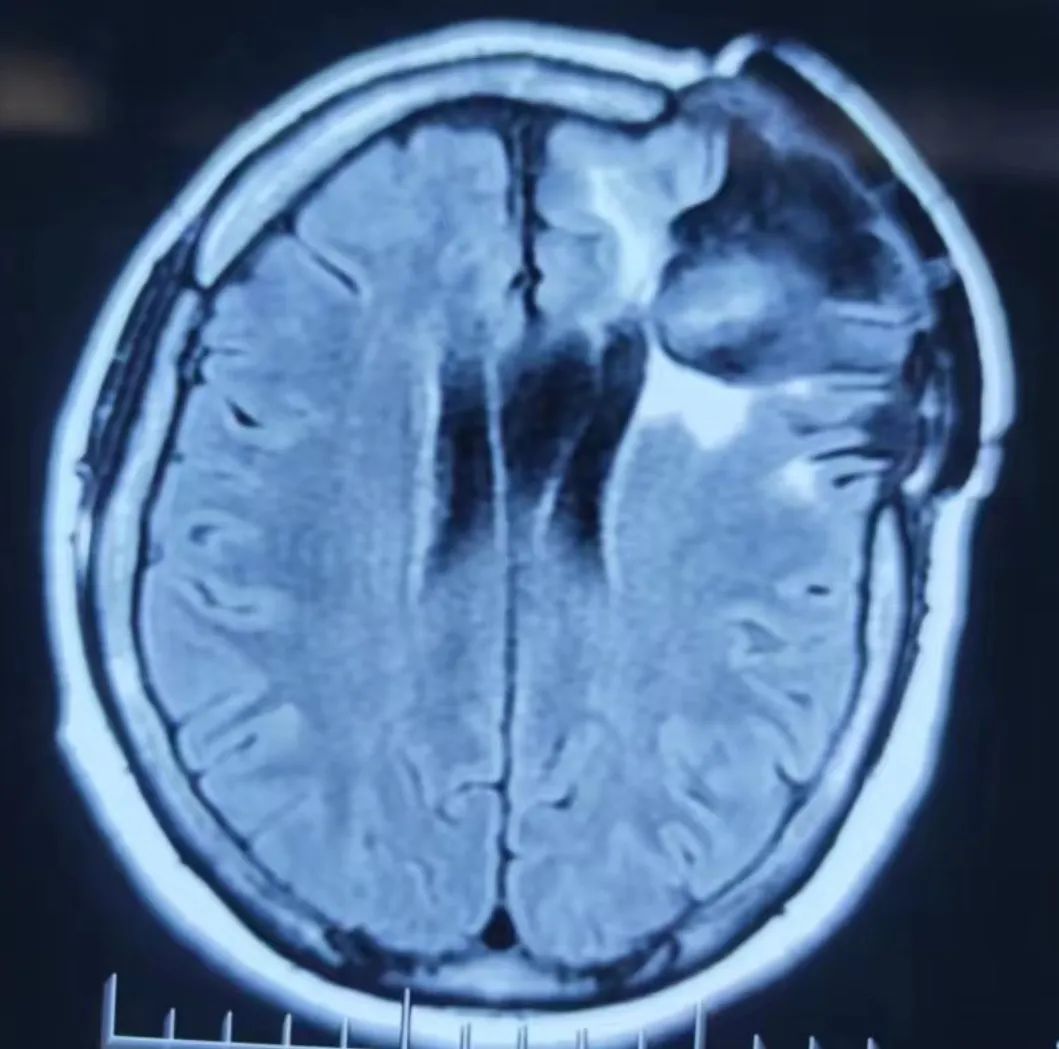

患者入院后完善顱腦癲癇序列磁共振、視頻腦電圖等相關(guān)檢查,確診患者為額葉癲癇(復(fù)雜部分性發(fā)作繼發(fā)全面強(qiáng)直陣攣發(fā)作),額葉失神發(fā)作。神經(jīng)外科副主任醫(yī)師王明義結(jié)合患者既往病史,發(fā)現(xiàn)其長期服用大劑量的抗癲癇藥物治療,但仍難以控制癲癇發(fā)作,考慮為藥物難治性性癲癇。對(duì)于藥物難治性癲癇,往往需要手術(shù)治療,而精準(zhǔn)定位癲癇病灶并切除是手術(shù)成功的關(guān)鍵。

與家屬充分溝通后,完善相關(guān)術(shù)前檢查,手術(shù)由癲癇外科專家王明義副主任醫(yī)師主刀,在麻醉科、手術(shù)室、影像中心、神經(jīng)電生理科、神經(jīng)外科等醫(yī)護(hù)人員的通力配合下,精準(zhǔn)定位了患者的致癇灶,用嫻熟的技術(shù)順利切除癲癇灶并對(duì)顱骨修補(bǔ)材料進(jìn)行了更換。術(shù)中患者神經(jīng)功能保護(hù)完好。